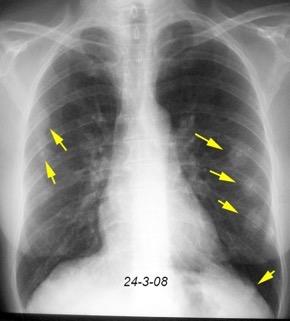

Carcinoma de mama con derrame pleural e implantes metastáticos